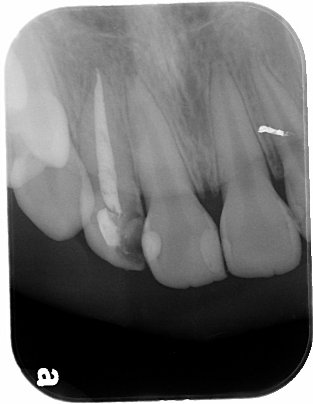

根管內稍做修形後放入玻璃纖維釘柱 , 修形為全瓷冠需要的牙齒形狀後(見圖三),再以雙線排齦方式排齦後印模 , 並以數位照相及電腦比色機比色. 一週後 , 於診間試戴無誤後 , 以永久黏著劑黏上 . 美觀與自然程度符合病人的需求 . 外形如圖四所示

圖四 |

以下為為全瓷冠復形後全貌.